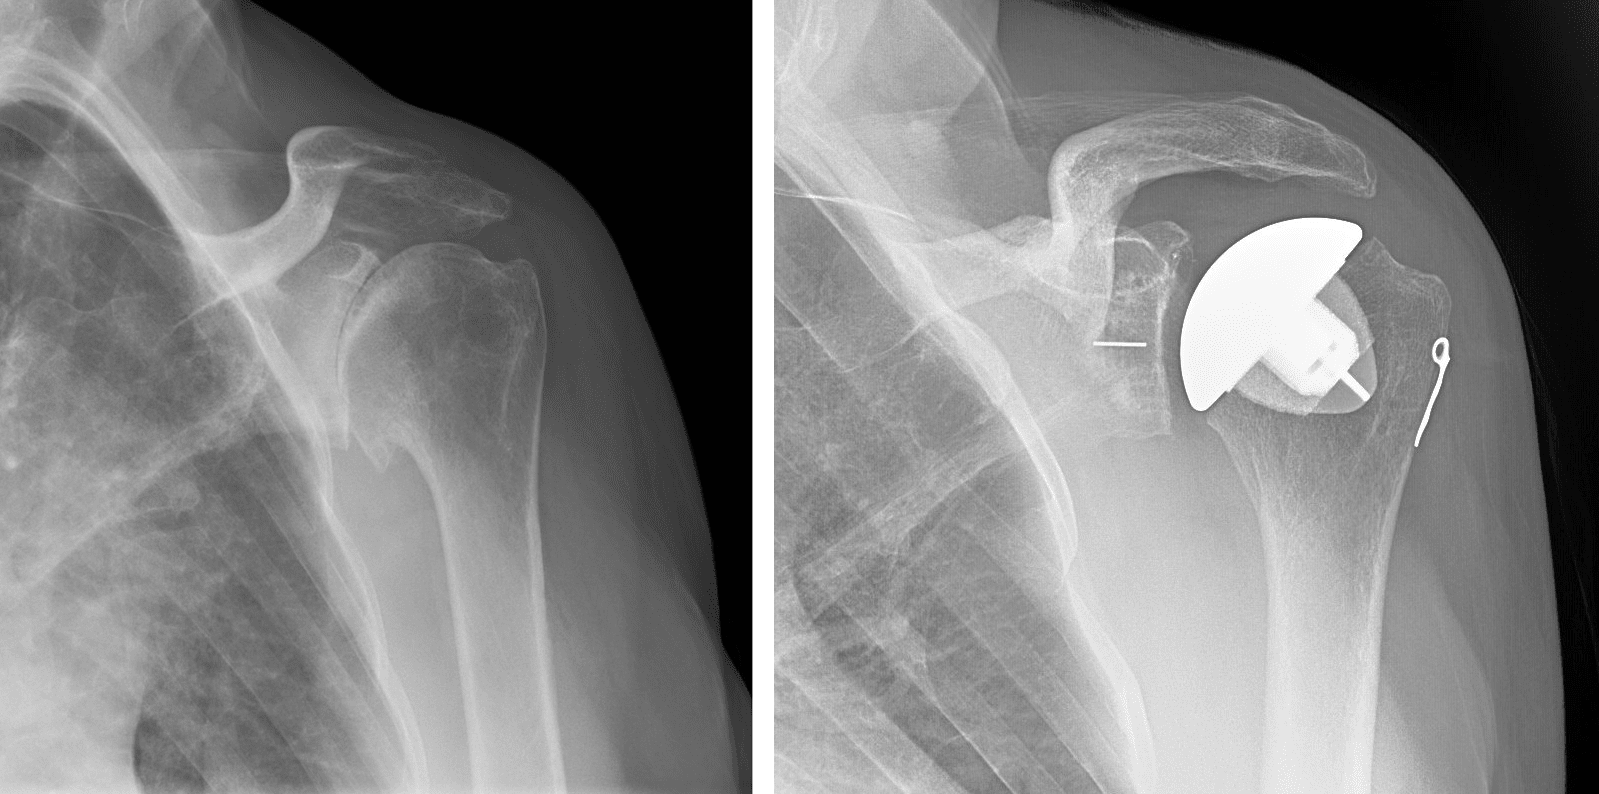

Shoulder replacement is a surgical procedure designed to relieve pain and restore function in severely damaged shoulder joints, typically due to arthritis, fractures, or degenerative joint diseases. During the procedure, the damaged parts of the shoulder, including the humeral head (ball) and sometimes the glenoid (socket), are replaced with artificial components made of metal and plastic. This surgery is often recommended when non-surgical treatments like medication and physical therapy fail to provide relief. Shoulder replacement can significantly improve mobility, reduce chronic pain, and enhance the overall quality of life, especially for patients with limited shoulder movement and persistent discomfort.